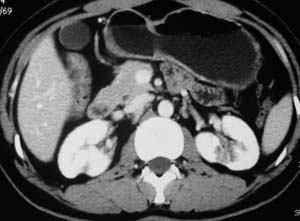

以下是引用子期在2010-3-19 20:47:00的发言:[br]血管畸形的ct增强应该有明显强化,本例并不相符合。本例双肾局部的略低密度影,累及肾盂,局部皮质明显变薄、内陷,增强扫描有轻度的强化,应考虑为炎性病变,患者为年轻男性,累及双肾的感染以结核较常见,可以没有明显的临床症状,尿中有时候也并不能查出什么;肾脓肿常有明显感染中毒症状,本例不符,另外一般的肾盂肾炎或肾小球肾炎通过小便就可确诊,其它还不能排除的是黄色肉芽肿性肾盂肾炎,然而单凭ct一般也很难鉴别。